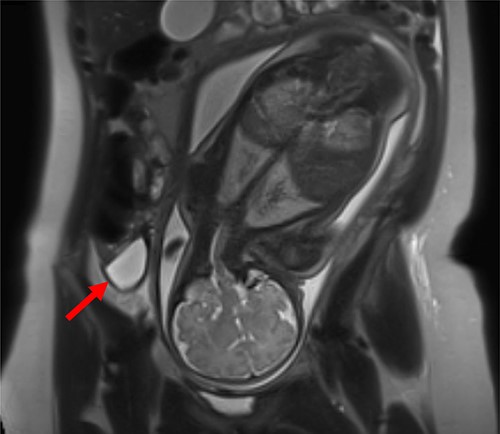

Patient 1 (31 years, 35 + 4 weeks of pregnancy) was suffering colicky pain in the right lower quadrant accompanied by symptoms of nausea, emesis, and an episode of diarrhea since the night before. Clinical examination revealed strong pain with guarding upon palpation of the right lower abdomen. Blood tests showed no abnormalities. Pregnancy-related causes were excluded by gynecological examination; cardiotocography and fetal ultrasonography were both physiological. An urinary infection was suspected, so the patient was hospitalized and intravenous antibiotic treatment (co-amoxicillin) initiated. Two days after admission, an MRI revealed a fluid collection in the right lower abdomen. The appendix could not be delineated clearly (Fig. 1).

MRI of patient 1 revealing a fluid collection in the right lower abdomen.